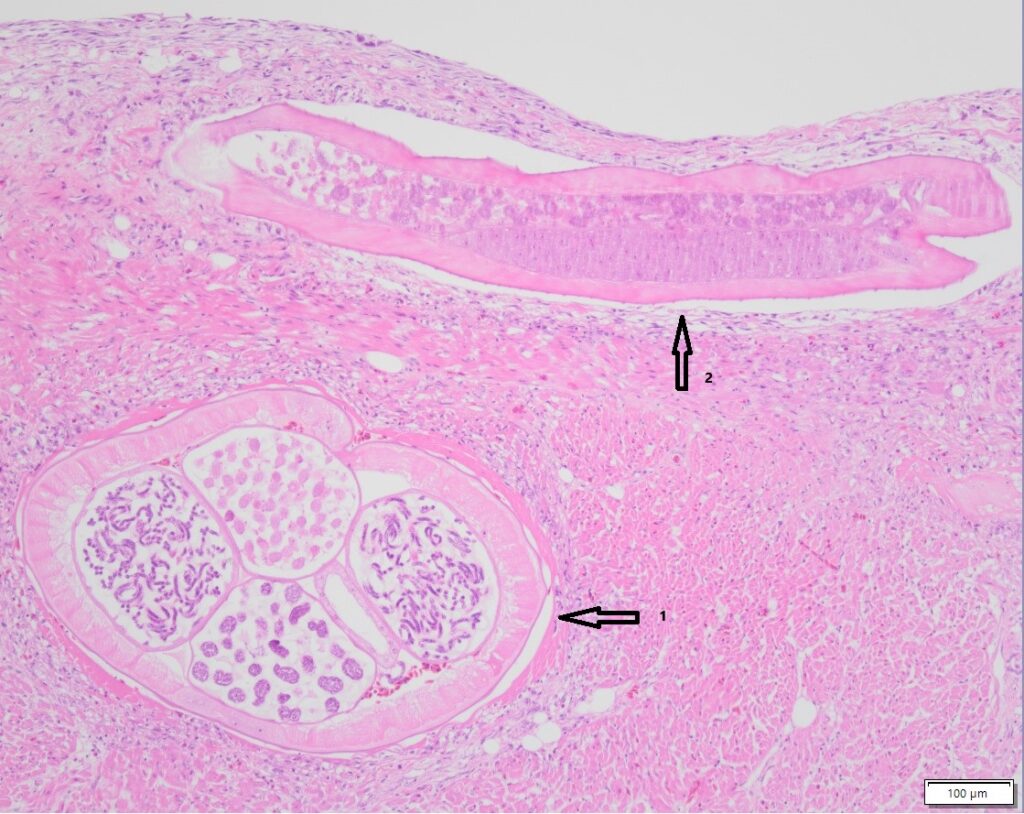

1. Cross section of the Trichobilharzia worm

2. Longitudinal section of the Trichobilharzia worm

Over the past few months, a number of these swans from Friesland and South-Holland, among other places, have been brought to Utrecht for further research. A flatworm Trichobilharzia spp. was found in the blood vessels of these animals (see figure 1). This worm is mainly found in ducks and swans. The parasites penetrate the bird’s body through the skin and cause inflammation in the blood vessels of various internal organs, such as the intestines and the brain. The damage that the parasite causes to the nervous system leads to abnormal behavior in the birds. The worm can also end up in the eye, causing the birds to become visually impaired or even blind.